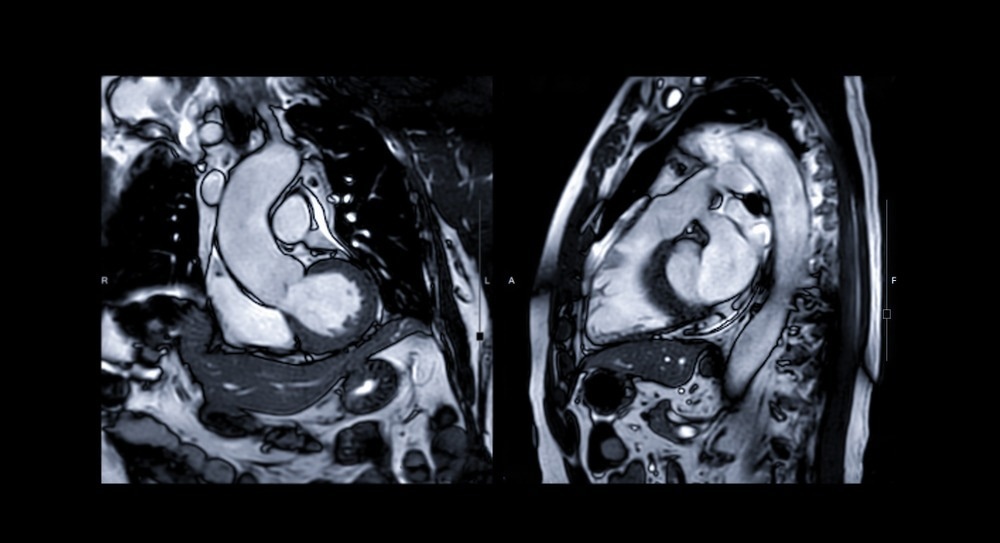

In recent years cardiovascular magnetic resonance imaging (MRI) has been recognized as a highly sensitive and specific tool for diagnosing myocarditis. This imaging technique has the unique potential to precisely visualize tissue changes, with the prospect of detecting characteristic changes in myocarditis – including interstitial and intracellular edema, hyperemia, capillary leakage, and (in more severe cases) cellular necrosis and ensuing fibrosis.

Contrast-enhanced MRI can also play a significant role in discriminating myocarditis from myocardial infarction, aiding in the evaluation of acute chest pain. In myocarditis, the infiltrates are usually located in the mid-wall and tend to spare subendocardial tissue, whereas the subendocardium is involved first in infarction. New contrast techniques using segmented inversion recovery gradient-echo pulse sequences and gadolinium enhancement can distinguish between diseased and normal myocardium even better.

Cardiac MRI

Image Credit: Radiological imaging/Shutterstock.com